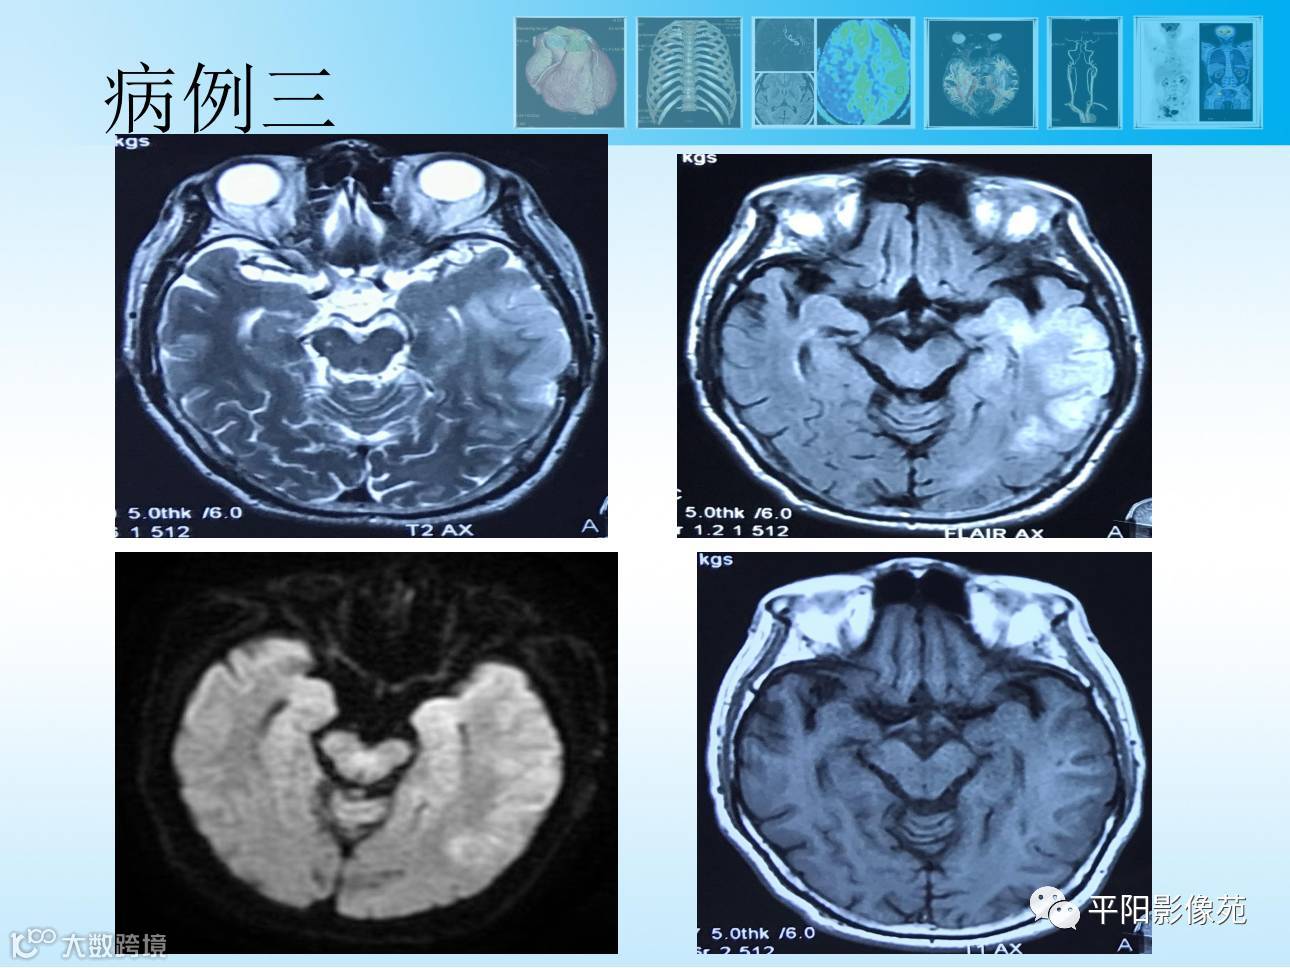

【MR功能成像专题2】3D-ASL灌注成像篇

导读:动脉自旋标记ASL成像,是一种完全无创的、不需注射造影剂的灌注成像方法,临床应用广泛。